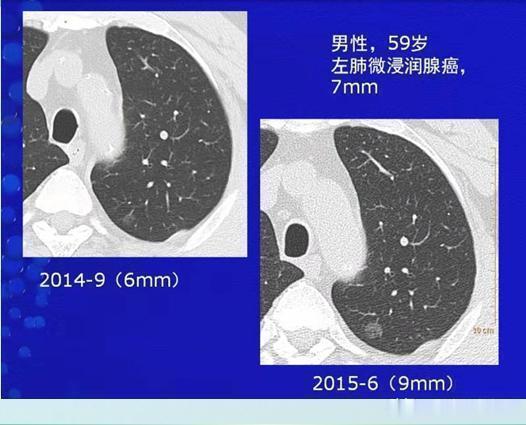

这是一位59岁的男士,体检发现左肺纯磨玻璃结节,直径6mm,随访观察逐渐增大,9个月后增大到9mm,手术病理是浸润性肺腺癌。例2,磨玻璃结节,增长迅速,病理为浸润性肺腺癌